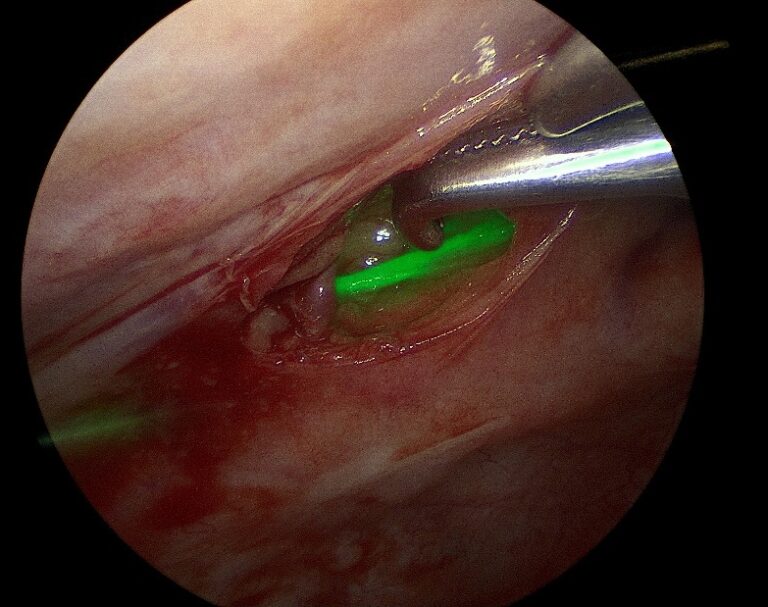

관절경 Arthroscopy 관절

관절경은 작은 절개를 통해 관절 내부에 카메라(관절경)를 삽입하여 병변을 직접 확인하고, 치료하는 최소침습 수술입니다.

주요 적용증은 십자인대 파열, 연골 손상, 관절 내 이물 등 입니다. 정확한 진단과 동시에 치료가 가능해 수술 효과가 높고 회복이 빠르며, 통증과 출혈이 적다는 것이 큰 장점입니다

관절경

관절경 장비 및 시술 장면 이미지